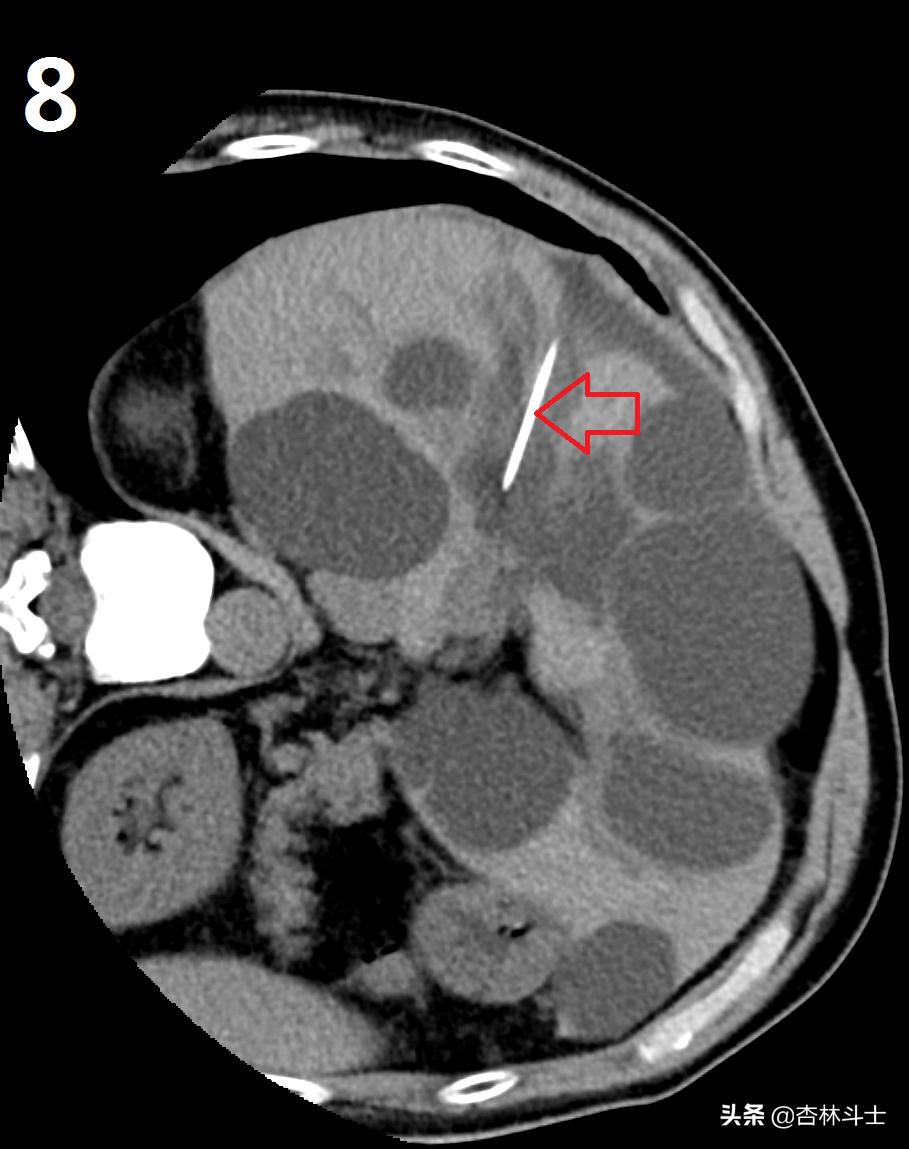

图7-8-9为上次做微创手术术中部分图像,红箭头所示为超细酒精抽吸硬化针,直径约0.79㎜,图9中五角星为囊腔内囊液被抽吸干净,最后一幅图是抽出来的黄色清澈囊液。同时被注入的无水酒精所代替。